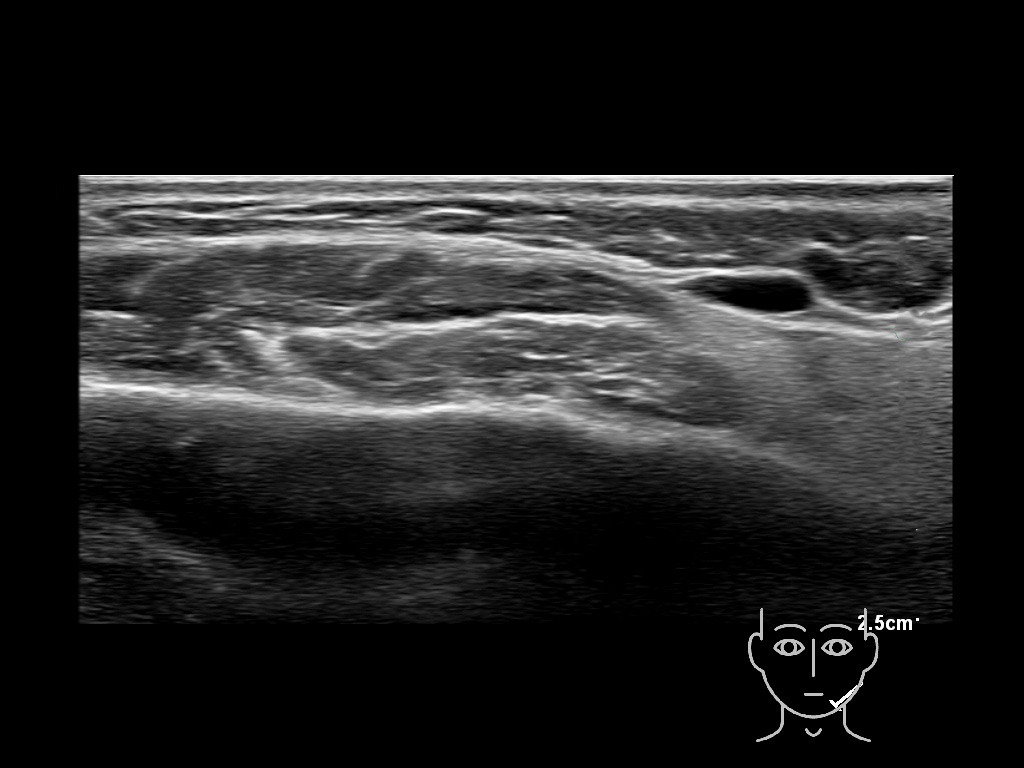

Study the first image to recognize the different layers. If you are sure about the layers, swipe to the second image to view the answer (if applicable).